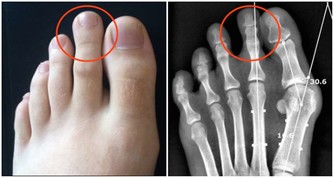

有著神奇的功效,對於治療中西醫束手無策的痛風,卻有令人無法想像的療效,只要早晚飲用一顆新鮮椰子水,即使痛風情況嚴重到骨關節變形,依然可以康復。 藥書泰斗嘉眾草師表示,根據統計發現,國人尿酸過高的情形日趨嚴重,而尿酸過高的患者極有會發展成痛風。 高尿酸的形成主要原因有二: 一、尿酸產生過多; 二、尿酸排泄減少。許多患者只有血清尿酸鹽濃度的增高而沒有臨床症狀,只有在發生關節炎時才稱為痛風。痛風的病理基礎是高尿酸血症,正常人血尿酸值是男性2.4-7mg/dL,女性1.6-5.2mg/dL。 當體液中尿酸濃度超過此值時,將因過剩而在組織中沈積,這種尿酸鹽的結晶沈積在關節滑膜、關節骨、軟骨而導致痛風性關節炎,沈積在皮下則形成痛風石。 中西醫均會要求痛風患者不可以攝取高普林食物,然而這些食物可以說是最起碼的美食,要痛風病患完全不吃這些食物,說真的,這種治療的犧牲代價還不小呢! 他們所提供的忌食食物包括有:雞、鴨、鵝、豬等內臟,以及魚、黃豆、發芽豆類、含酵母的飲料如養樂多、啤酒、豆苗、黃豆芽、蘆筍、紫菜、香菇、肉汁、濃肉湯、牛肉汁、雞精、酵母粉、健素糖等。 以上的食物對痛風患者來說,每一樣都必須忌口,那麼在飲食的享受上,他們都被排除在外,甚至平時可選擇的食物,必須去掉一大半以上,那麼人生還有什麼意義呢? 嘉眾草師以編著《小偏方治大病》、《草藥驗方大全》、《補酒藥酒大全》、《漢方治百病》、《癌症驗方大全》等等大部頭醫藥叢書聞名於世,他提供的驗方無不受到民眾的好評,為了對付中西醫束手無策的痛風,嘉眾草師特別介紹椰子食療法,患者只要每天飲用一至三粒新鮮椰子,一至兩個小時痛風就不再疼痛,連續飲用二至三個月,症狀即可消除。 如果沒有新鮮椰子,剝殼椰子也可以,每個約在廿至四十元之間。萬一購買不便,則改喝罐頭半天水、椰子水也可以,不過還是以新鮮椰子療效最好。 嘉眾草師表示,許多人耽心椰子會不會太涼?其實這是多慮了,因為患有痛風的人,本身體質會偏燥,高普林會不斷累積,椰子水正好可以清洗積存的痛風石,這是西藥秋水仙很難做到的。

痛風的確是一種令病人非常痛苦的一種病症,當它發作的時候,可以說是「痛不欲生」,這種毛病還真會整人,它發作時間通常是選擇在夜深人靜的時刻。青木瓜泡茶加新鮮椰子汁:痛風再見了!